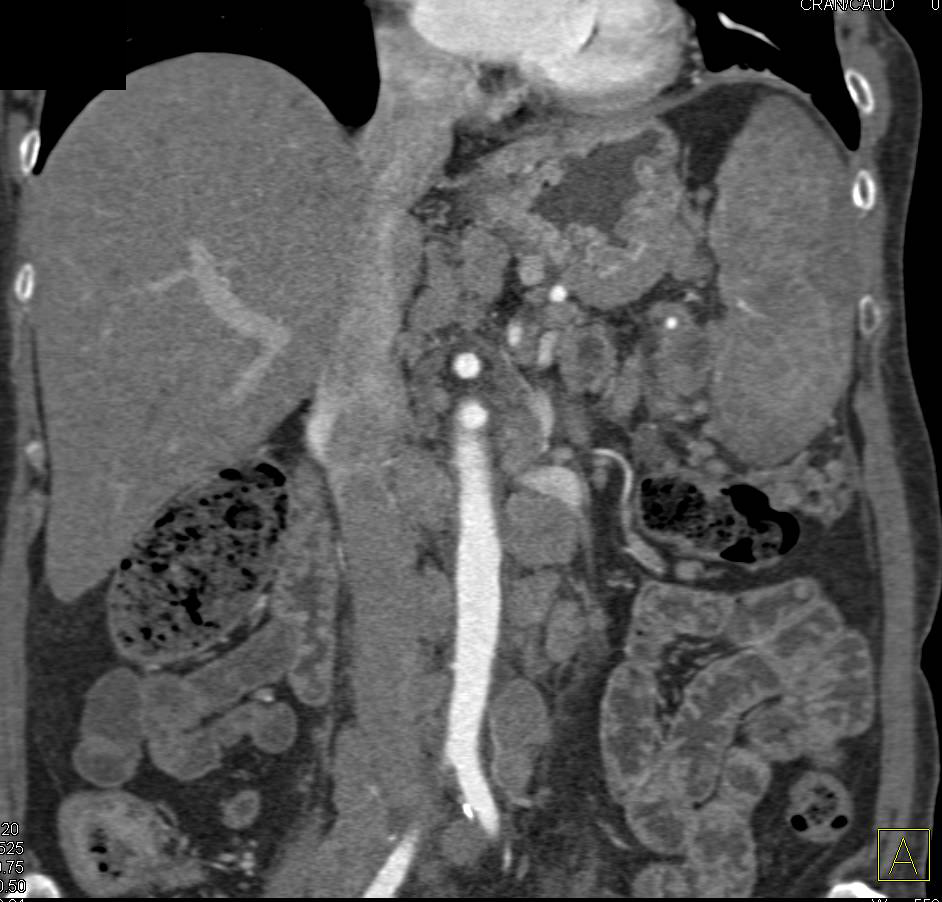

Crohn's Disease Ileum with Comb Sign with Prominent Vasa Recta